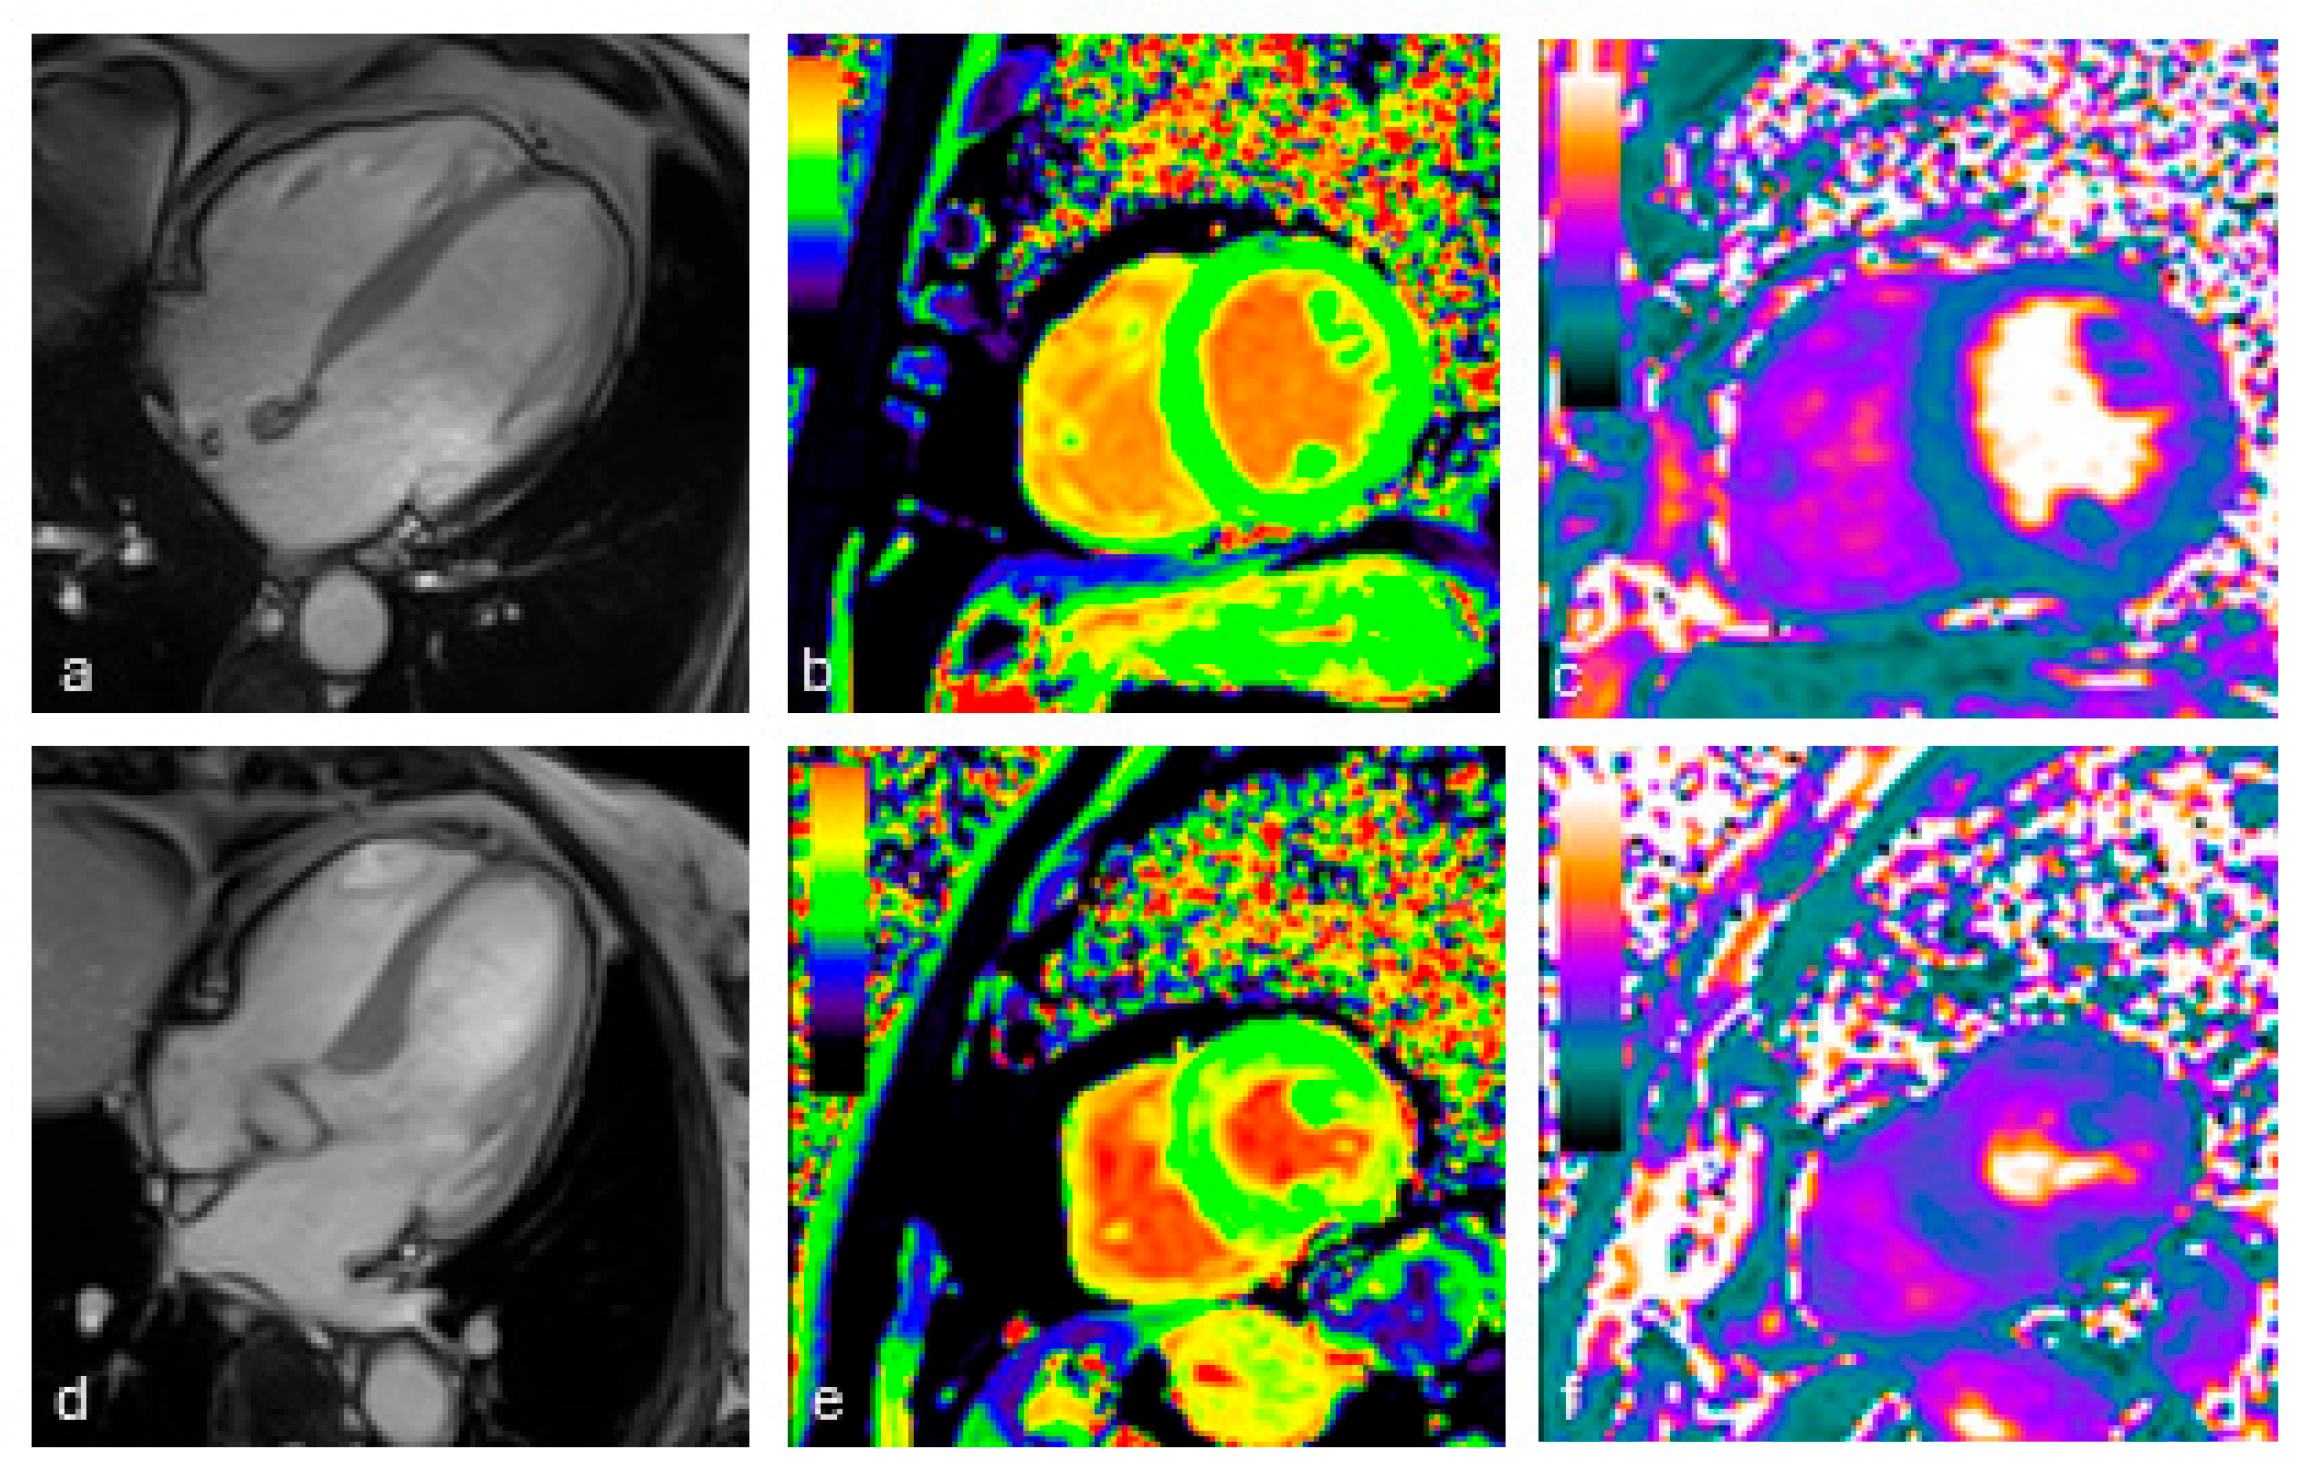

2.4. Cardiac MRI Protocol

2.4.1. Image Acquisition

2.4.2. Image Analysis

3.2. MRI Findings